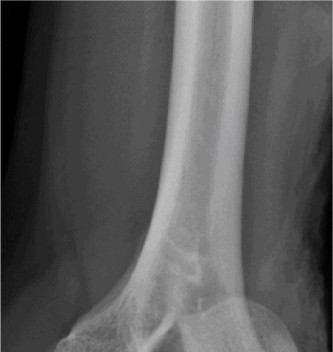

Treat a patient with infected total shoulder arthroplasty? CASE 21 A 70-year-old, right-hand-dominant female presents to clinic complaining of 4 years of gradually worsening chronic right shoulder pain and stiffness. She says the pain is worse at night and with any range of motion, denies a history of trauma, pain in other extremities, or numbness or tingling of the right upper extremity. She notes that her mother suffered from rheumatoid arthritis that affected her shoulder. Physical examination reveals decreased muscle bulk over the right supra- and infraspinatus fossae compared to the contralateral side, limited active and passive ROM, marked weakness with external rotation, and 4+/5 strength with shoulder abduction. X-rays of the right shoulder are shown in Figures 2–58 and 2–59.

Figure 2–58

Figure 2–59

The correct answer is (C). Rotator cuff tear arthropathy consists of a combination of rotator cuff insufficiency, glenohumeral joint degenerative changes, and superior humeral head migration. It is more common in women and also more often found on the dominant side. The patient’s clinical examination with weakened external

rotation and muscle atrophy signaling incompetent supra- and infraspinatus muscles point to rotator cuff insufficiency, and her plain films reveal narrowed glenohumeral joint space as well as superior migration of the humeral head. Choice D is incorrect because, while radiographs would show narrowing of the glenohumeral joint space, they would also likely show numerous osteophytes and posterior wear of the glenoid. Choice B is incorrect because, while adhesive capsulitis does present as decreased active and passive range of motion, the patient’s constellation of symptoms pointing towards rotator cuff insufficiency along with the radiographs make cuff tear arthropathy the more likely choice. Finally, Choice A is incorrect because even though she has a positive family history of rheumatoid arthritis, it is less likely to present only in a single joint. Also, rheumatoid arthritis on radiography appears more as an erosive process without the characteristic superior migration of the humeral head.

The correct answer is (A). Superior migration of the humeral head would be most indicative of chronic rotator cuff insufficiency associated with cuff tear arthropathy, as it is a direct result of the inability of the rotator cuff tendons to help maintain the humerus in its normal position. Acetabularization of the undersurface of the acromion is commonly associated with superior migration of the humeral head found in rotator cuff tear arthropathy, and can be assessed using the Hamada classification, which is based on measurements of the acromiohumeral interval on radiography (Table 2–8). Choices B and C are incorrect because, while narrowed glenohumeral joint space and subchondral sclerosis are associated with rotator cuff arthropathy on radiographs, they indicate degenerative joint changes rather than chronic rotator cuff insufficiency. Choice D is incorrect because it is not a specific sign of rotator cuff arthropathy.